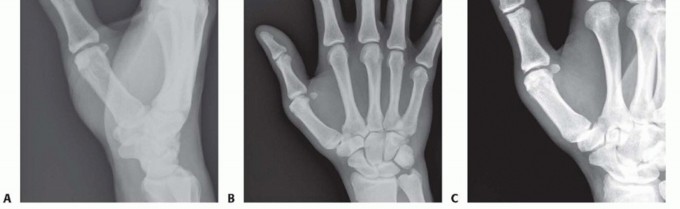

FIG 1 • Anatomy of the thumb MP joint. Thumb MP joint motion varies widely from individual to individual because of the spectrum of metacarpal head geometry seen in “normal” hands.Some metacarpal heads are more rounded and allow greater flexion, extension, and rotation, whereas others are flatter and allow relatively less range of motion (ROM).The joint derives its stability mostly from soft tissue constraints not bony architecture (FIG 1).The proper collateral ligaments originate from the region of the lateral condyles of the metacarpal and pass palmarly and obliquely to insert on the palmar portion of the proximal phalanx.The accessory collateral ligaments originate from the same region but slightly more proximal and traverse distally and palmarly in an oblique fashion to insert on the volar plate and sesamoids.The volar plate serves as the floor of the MP joint. The adductor pollicis (AdP) inserting into the ulnar sesamoid at the distal edge of the volar plate and the insertions of the flexor pollicis brevis (FPB) and abductor pollicis brevis (APB) into the radial sesamoid at the radial distal edge of the volar plate provide additional volar support.The AdP, FPB, and APB also contribute fibers to the extensor mechanism by way of the adductor and abductor aponeuroses and thus provide a modicum of lateral joint stability.P.419Dorsally, the extensor pollicis brevis inserts onto the base of the thumb proximal phalanx and the extensor pollicis longus inserts at the base of the thumb distal phalanx; both traverse the MP joint and add to the stabilizing forces surrounding the joint.The MP joint capsule itself surrounds the joint and contributes slightly to stability.

FIG 2 • X-rays showing MP joint dislocation on AP (A) and lateral (B) films. (continued)